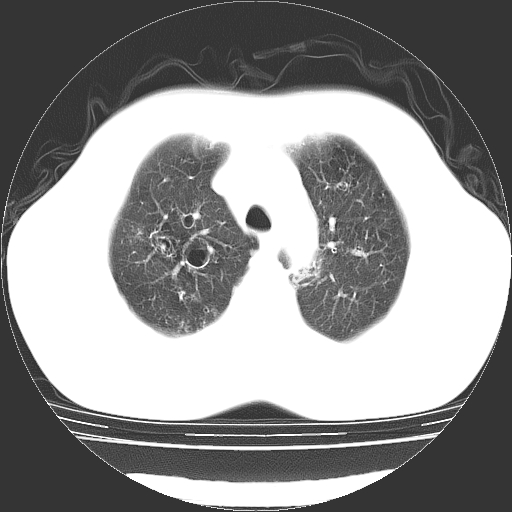

以下是引用zyx168在2006-12-4 15:30:00的发言:[br]经典!支气管肺囊肿并感染。

以下是引用dyqct在2006-12-4 17:11:00的发言:[br]典型的囊状支扩合并感染。

以下是引用liaoqiang在2006-12-4 16:12:00的发言:[br]局部肺叶内可见扩张的支气管壁,考虑为支扩。部份囊样影内有小液平和肺内散布斑片征影、小结节及纤维灶,提示支扩伴感染,且由于局部呈现有树芽征感染以结核可能性大。

以下是引用zhoucan076在2006-12-4 16:48:00的发言:[br]囊状支扩合并感染